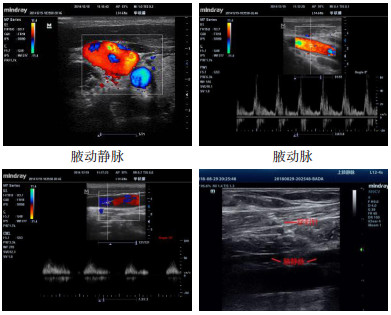

1.2.2 穿刺方法(1)Magney穿刺法按Magney提出的体表定位法[4]选取定位点。先取两条线:一条是胸骨角中心与肩胛骨喙突的连线,取其中外1/3交点为进针点;另一条是胸锁关节与肩锁关节的连线,取其中内1/3交点为目标点。目标点为腋静脉与锁骨下静脉移行处,即腋静脉上段。穿刺针与胸壁呈30°~45°负压缓慢进针,靶点处刺入静脉,进针深度参考锁骨和第一肋骨间隙。见图 1[4]。(2)超声引导穿刺法:在锁骨中内侧部分下方,局部加压或应用脉冲多普勒波形确认动静脉。静脉容易压扁,波形平坦,动脉搏动感强,波形高尖。探头长轴放置于静脉上,穿刺针与胸壁呈30-45°负压缓慢进针,通过超声显示器明确针道进入静脉,穿刺针内见暗红色血液。见图 2。

| 图 2 超声引导下腋动静脉及穿刺图示 Fig 2 Ultrasound-guided axillary arteriovenous and puncture graphics |